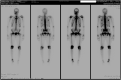

The present case report is aimed to highlight the difficulty and the reason for the delayed diagnosis of phosphaturic mesenchymal tumors, emphasizing the need of standardized protocols for diagnosis, surgery and follow-up in high-volume hospitals. The clinical signs and symptoms, diagnostic and therapeutic procedures, immunohistological features were analyzed. Delayed diagnosis of phosphaturic mesenchymal tumor was primarily due to non-specific clinical symptoms such as fatigue, muscular and bone pain, and multiple fractures. This cryptic clinical picture made the diagnosis tricky that led to treatment of patient for non-specific pain and stress fractures before to consider the tumor-induced osteomalacia syndrome. Some well-documented studies were found in the literature in which the history of trauma is a critical trigger of glomus tumors. Extra-subungual tumors most frequently occur in the knee and ankle regions, particularly among young adults, and the diagnosis is typically made approximately 7.2 years after initial symptom onset. The difficult tumor localization represented an additional obstacle to the prompt treatment, leading to delayed curative surgery.